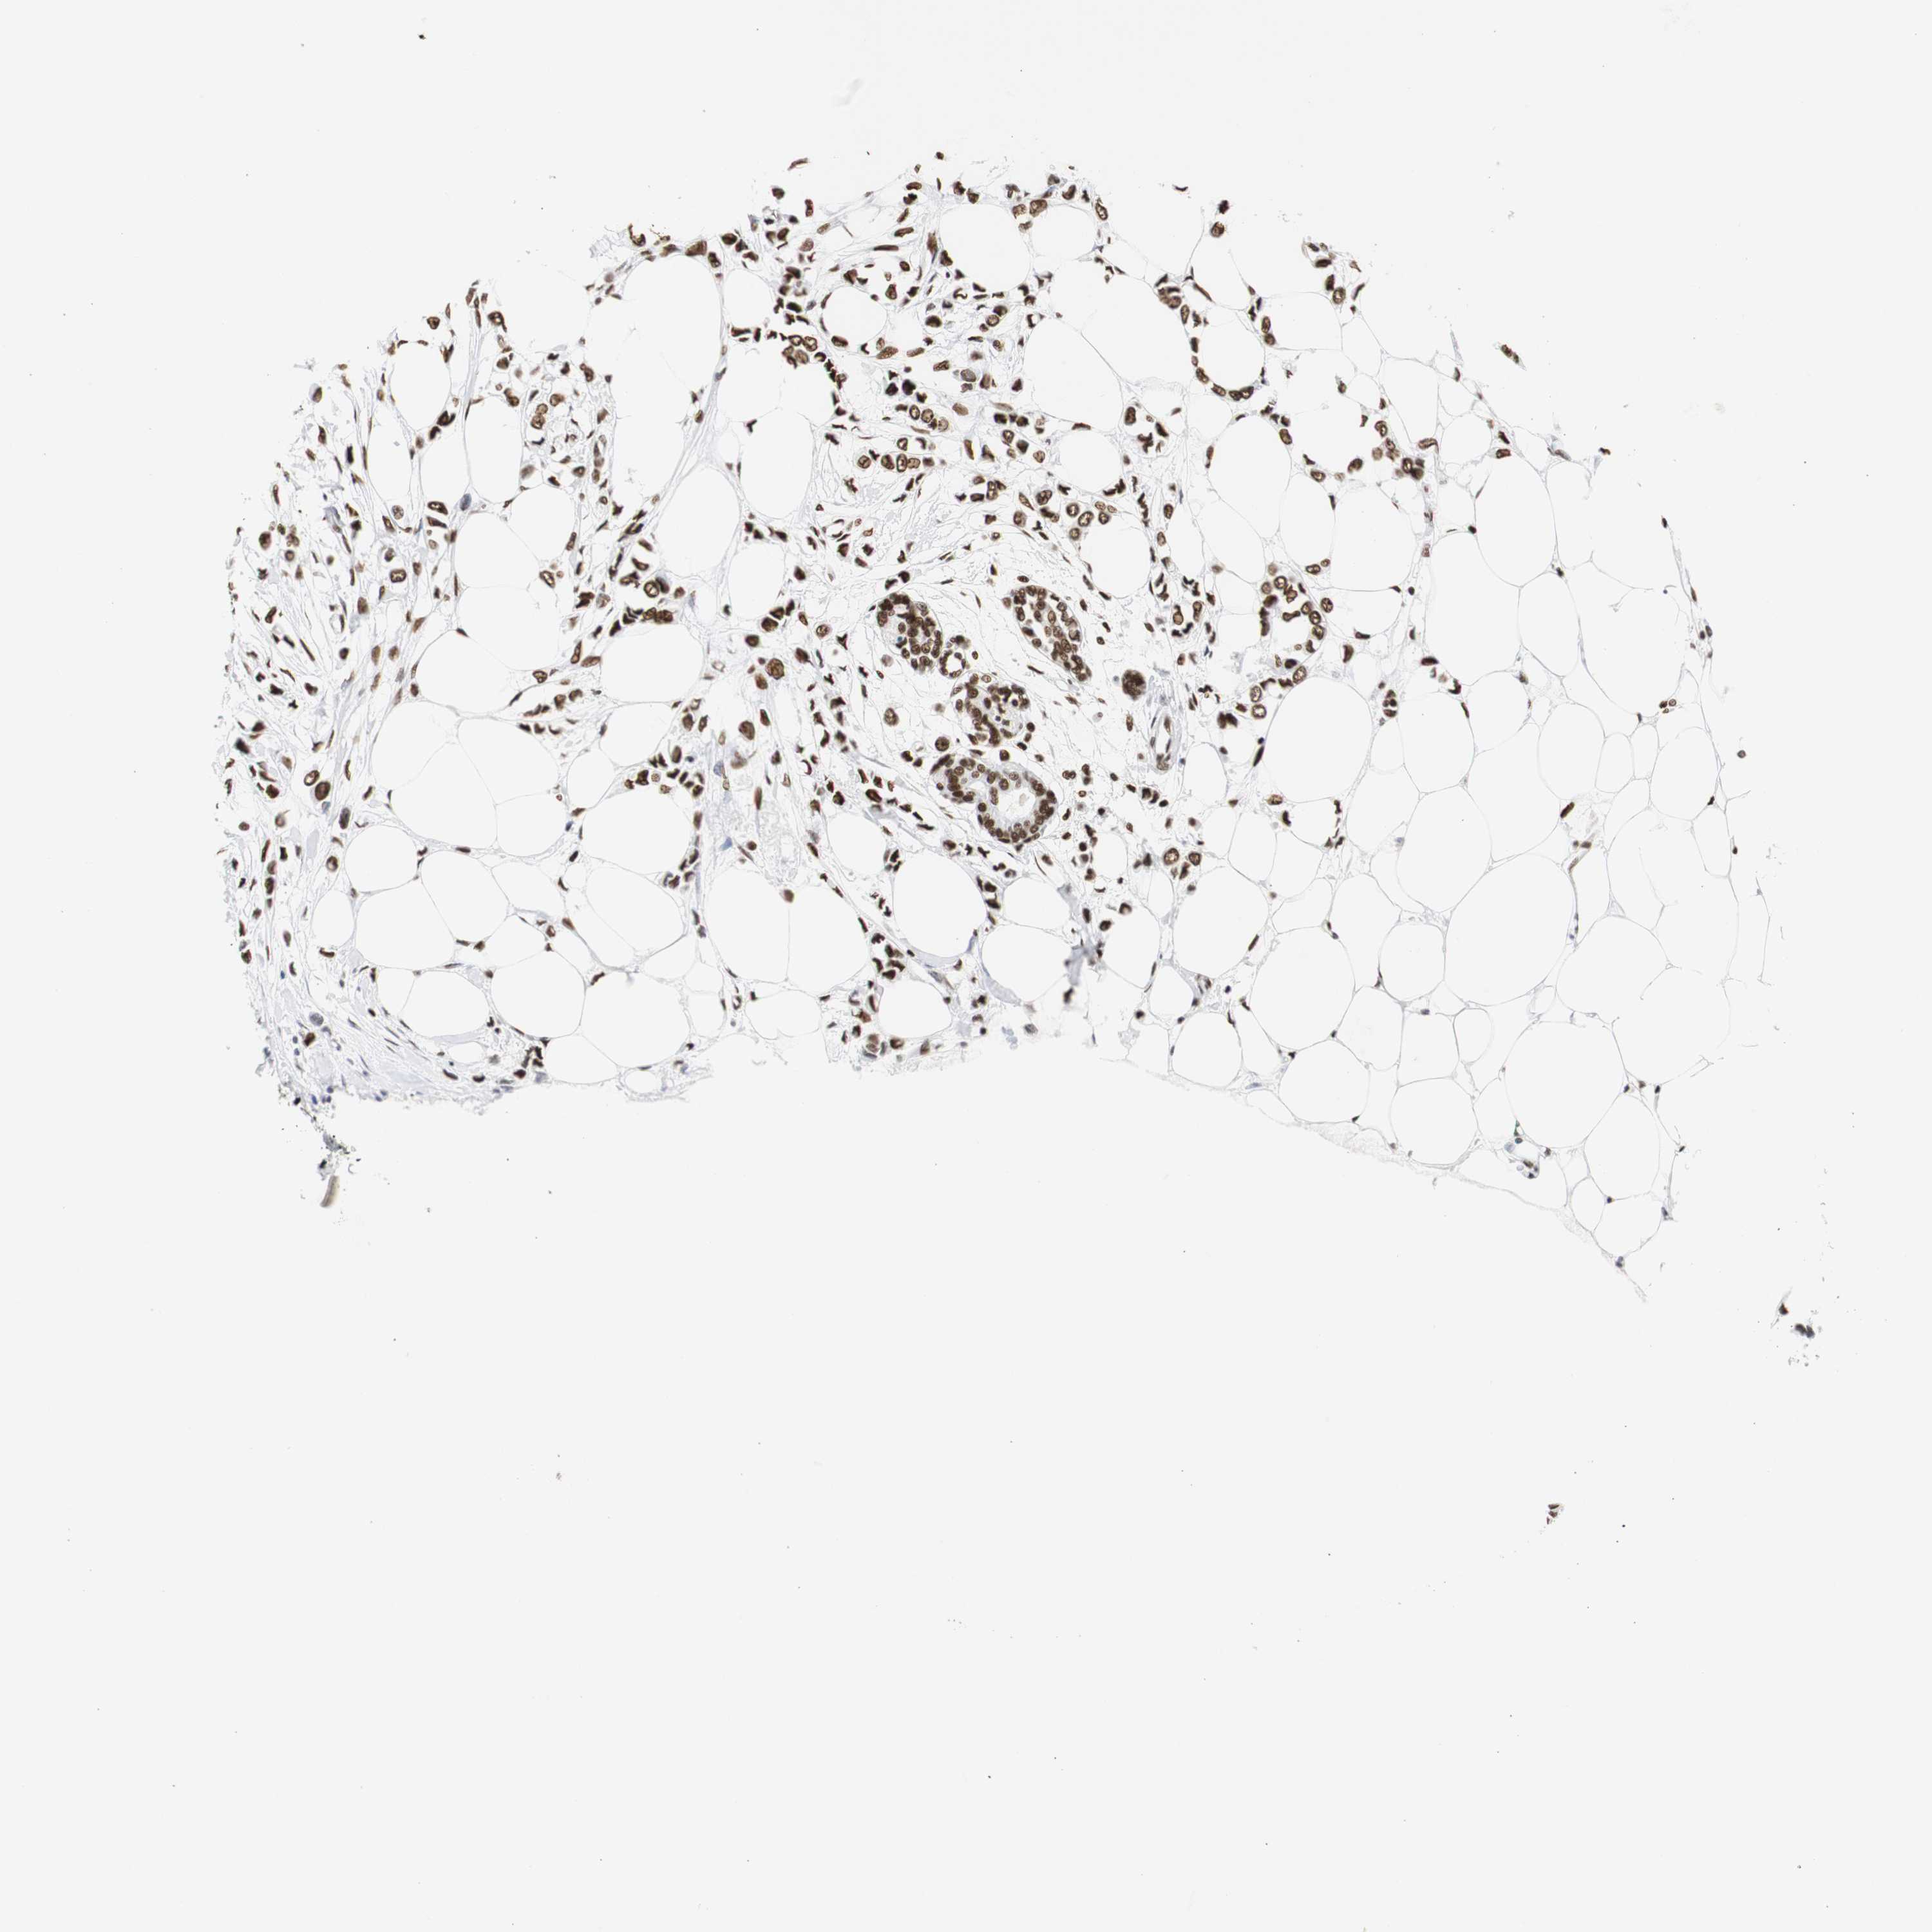

BRCA TCGA BRCA VALIDATION PROTEIN EXPRESSION